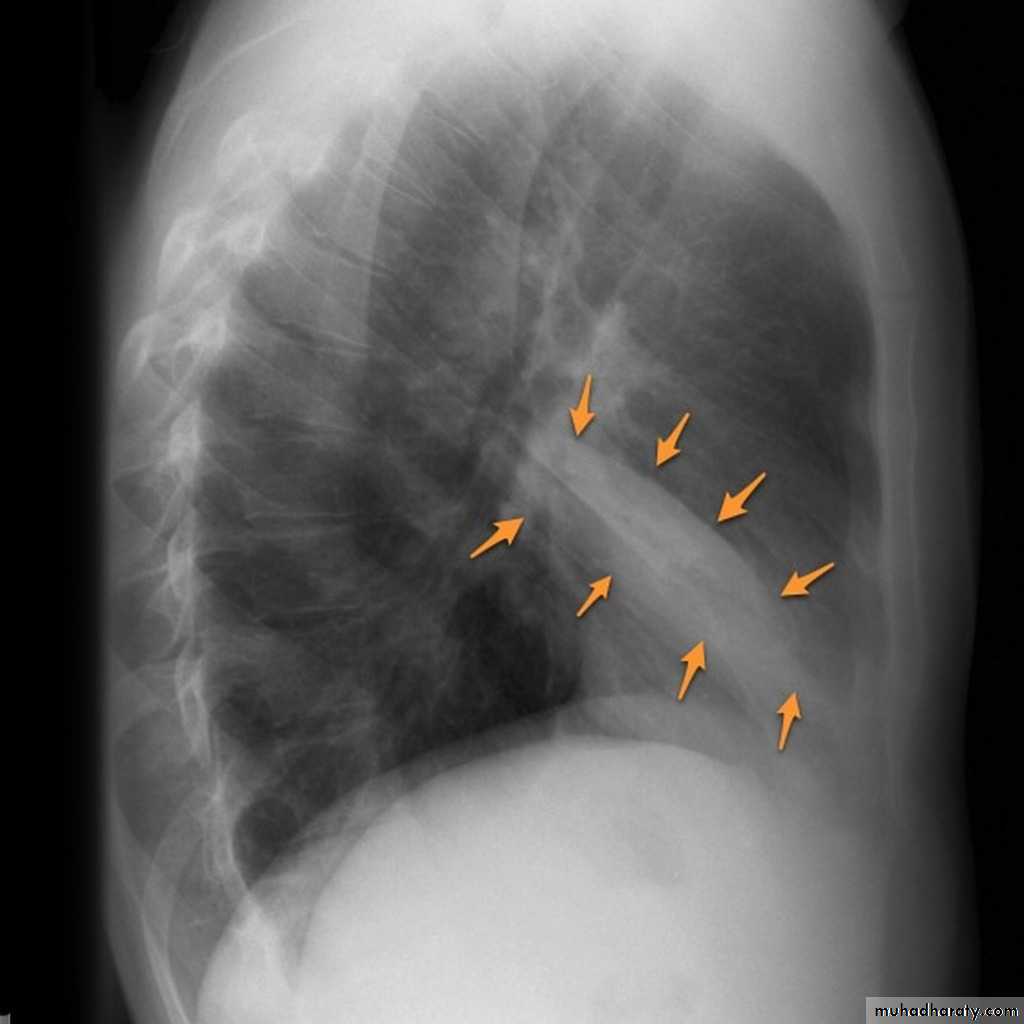

Right middle lobe collapse has distinctive features, and is usually relatively easily identified.

Radiographic features

Chest radiograph

Frontal chest XR showing opasity cause obscuration of the RT cardiac border

Lateral chest XR film the opacity is tongue like shape

versus (triangular in shape) in RT middle lobe consolidation seen in lateral chest XR film